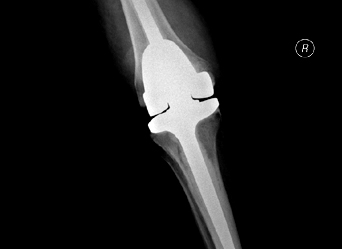

xray of a successful Total Knee ReplacementIn knee replacement surgery (arthroplasty) a damaged, worn or diseased knee is replaced with an artificial joint. There are two main types of surgery, depending on the condition of the knee: total knee replacement and half (partial) knee replacement. It is an effective procedure that reduces pain and improves quality of life. Materials used for replacing the joint are strong and durable but also optimal for joint function as they produce as little friction as possible.